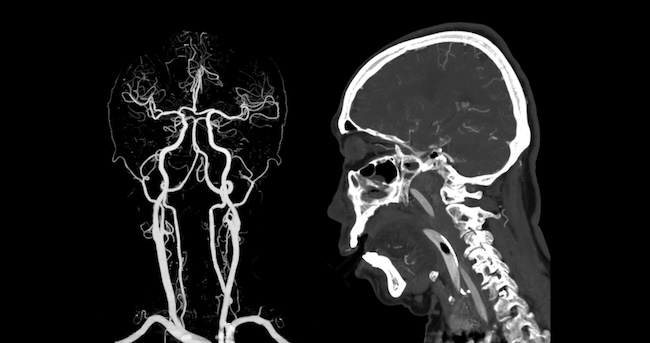

Extended CT angiography versus standard CT angiography for the detection of cardioaortic thrombus in patients with ischaemic stroke and transient ischaemic attack (DAYLIGHT): a prospective, randomised, open-label, blinded end-point trial

Latar belakang: Sumber kardioemboli seringkali masih tidak terdeteksi dengan metode diagnostik stroke standar sehingga kejadian rekurensi stroke tetap tinggi. Studi ini bertujuan menilai apakah pemeriksaan CT angiografi kepala dan leher yang diperluas hingga setidaknya 6 cm di bawah karina (CT angiografi diperluas) dapat meningkatkan angka deteksi trombus kardioaorta jika dibandingkan prosedur CT angiografi standar pada pasien stroke iskemik atau serangan iskemik sepintas.

Deteksi dini sumber kardioemboli sangat penting karena terapi antikoagulan bisa mencegah stroke berulang. Namun, sebagian besar sumber kardioemboli ini gagal terdeteksi oleh pemeriksaan diagnostik standar. Studi ini bertujuan menilai apakah pemeriksaan CT angiografi kepala dan leher yang diperluas hingga setidaknya 6 cm di bawah karina bisa meningkatkan deteksi trombus kardioaorta dibandingkan CT angiografi standar pada stroke iskemik atau TIA.

Tim peneliti terdiri dari dokter spesialis neurologi yang khusus mendalami stroke, dokter spesialis radiologi tersertifikasi kardiotoraks, dan dokter spesialis jantung. Perluasan area pencitraan mencakup bagian awal aorta torakalis, tempat umum terbentuknya trombus yang tidak terlihat pada CT angiografi standar yang hanya mencakup kepala dan leher.